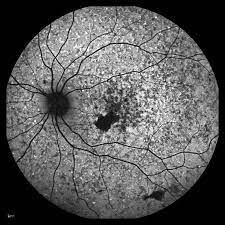

Name Mara Goldberg Cra Description Ophthalmology Ophthalmicphotography Autofluorescence Retina Stargardt S Disease Medical Art Optometry Eye Health